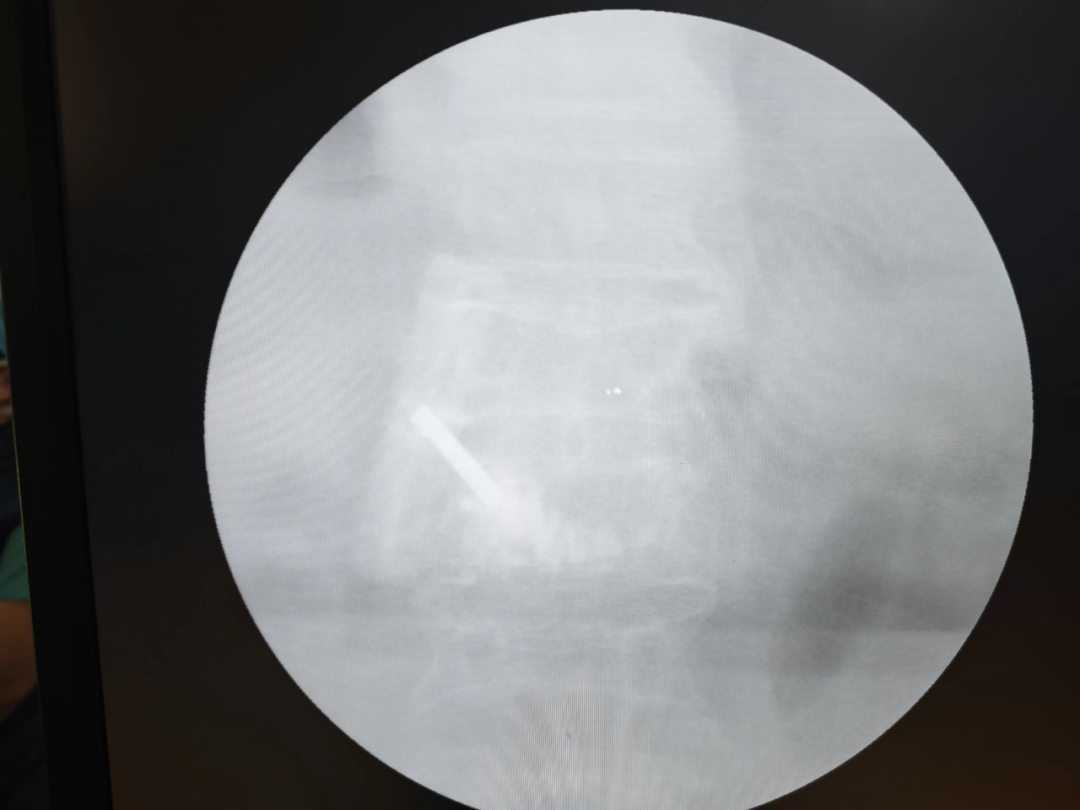

病例回顧 骨折部位 術(shù)中C臂協(xié)助定位 在C-臂監(jiān)視器透視下,分別定位胸12雙側(cè)椎弓根位置,標記穿刺點,僅以穿刺點為中心做3mm切開,在透視下注入骨水泥,再次透視見骨水泥位置良好。 骨水泥注入 術(shù)后影像學檢查 手術(shù)切口1cm左右 該手術(shù)經(jīng)皮透視下穿刺,手術(shù)切口小,創(chuàng)傷小,無需縫合,術(shù)后患者即感腰部疼痛明顯減輕,第二天可下床行走,已無腰痛不適,張大娘非常高興,自己再也不會受腰痛折磨整日與床為伴了。 我院脊柱骨科近年來,已成功開展多臺PVP手術(shù),為廣大老年患者減輕了病痛,減少了患者臥床時間,提高了生活質(zhì)量,是骨質(zhì)疏松性椎體骨折患者的福音。如果家里的老人突然出現(xiàn)了腰背疼痛,翻身下床困難,或者出現(xiàn)了腹部不適,排除腹部疾病(因為很多胸腰椎骨折患者在早期以腹痛腹脹為最主要癥狀),無論有沒有外傷史,建議帶老人及早就醫(yī),如果發(fā)現(xiàn)椎體損傷,積極治療,讓老人度過一個輕松愉快的晚年生活。 科普小講堂:經(jīng)皮椎體成形術(shù) 什么是骨質(zhì)疏松性椎體骨折? 骨質(zhì)疏松性椎體壓縮骨折,即在日常生活中患者并未遭受到明顯的外力而發(fā)生的骨折。這種骨折與創(chuàng)傷性的骨折不同,是由于自身骨質(zhì)疏松所導(dǎo)致的骨組織病變。骨質(zhì)疏松性骨折發(fā)生時,患者會感覺到背部明顯疼痛,翻身或起床等動作會讓疼痛更加明顯。 骨質(zhì)疏松性椎體壓縮骨折的危害有哪些? 一旦椎體發(fā)生骨質(zhì)疏松性椎體壓縮骨折,常常會導(dǎo)致患者出現(xiàn)腰背部持續(xù)性疼痛、季肋部放射痛、后凸畸形、呼吸功能受限及胃腸道癥狀等諸多癥狀,造成老年患者生活質(zhì)量下降。 什么是經(jīng)皮椎體成形術(shù)? (Percutaneousvertebroplasty,PVP)是一種新型的脊柱微創(chuàng)手術(shù),通過采用經(jīng)皮穿刺的方法,經(jīng)過椎弓根或是直接向椎體中注入骨水泥,使得椎體的強度和穩(wěn)定性得以提升,防止塌陷,從而達到緩解腰背疼痛,甚至部分恢復(fù)椎體高度的目的。 PVP手術(shù)優(yōu)點是什么? 1.恢復(fù)顯著:通常術(shù)后6個小時即能達到穩(wěn)定固定,患者可下床站立活動,大大縮短了患者臥床的時間。 2.疼痛減輕:術(shù)后患者會發(fā)現(xiàn)腰背部疼痛明顯減輕。 3.微創(chuàng):該治療方法僅需在皮膚上留2-3mm的穿刺針孔。 4.安全性:由于手術(shù)采用的是局部麻醉,因此即便是存在多種基礎(chǔ)病的患者也能夠耐受手術(shù),整個手術(shù)過程相對安全。 就診地址 酒泉市中醫(yī)醫(yī)院四樓脊柱骨科 咨詢電話 一樓門診部:0937-2669161 王醫(yī)生:13209409826 ??? 張醫(yī)生:18219971722